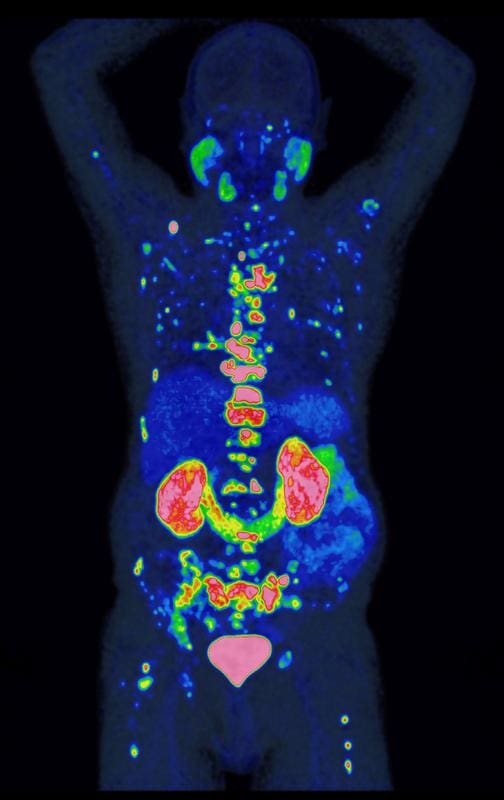

For the risk assessment, the PROMISE team used PSMA-PET, a state-of-the-art imaging technique that can be used to visualize prostate cancer cells with particular precision and their stage of spread in the body. Since the method is more sensitive than older procedures, its findings first had to be translated into new treatment recommendations – a process that PROMISE has significantly shaped. In one of the largest studies worldwide, the team evaluated image data from over 15,000 patients. Together with leading international research institutions, it developed the PROMISE scheme – a method that can be used to determine individual risk profiles on the basis of PSMA-PET much more precisely. Based on this, nomograms were created, i.e. predictive models for the individual risk, which are prepared in an understandable way for doctors and patients and can be used for joint therapy decisions.